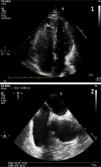

Blood test revealed a D-dimer level of 33,410 (normal<500). The electrocardiogram showed sinus rhythm at 80bpm, with a S1Q3T3 pattern. Arterial blood gas analysis revealed respiratory alkalosis and partial respiratory failure. PE was suspected, so a chest angio-CT scan was conducted (Fig. 1), in which direct evidence was observed of a massive PE that manifested as a partially recanalized thrombus straddling the two main branches, and bilateral thrombosis in segmental arteries, along with signs of right ventricular overload.

Given the suspected diagnosis of paradoxical embolism through a PFO, a transthoracic echocardiography and a subsequent transesophageal echocardiography were requested (Fig. 2). This revealed an aneurysm of the atrial septum with PFO, mild left ventricular hypertrophy and mild mitral regurgitation. Tricuspid regurgitation was not observed in any of the ultrasound examinations, so systolic pulmonary pressure could not be calculated. However, mild pulmonary insufficiency, with a mean pulmonary acceleration time of 140ms and normal mean pulmonary artery pressure of 20mmHg was detected. The diagnosis of left popliteal DVT and massive PE secondary to long traveling hours was established, with paradoxical embolism in the right arm due to PFO.

Image 1 (apical view of the four chambers obtained by transthoracic ultrasound): baseline image after injection of contrast material (agitated saline). Higher echogenicity is seen in the right ventricle and right atrium (more grayish color due to microbubbles) and, without the need of Valsalva maneuver, passive passage of microbubbles to the left heart occurs (small hyperechoic spheres). Image 2 (cross-sectional bicaval plane on transesophageal ultrasound): fossa ovalis membrane detachment of up to 3mm.